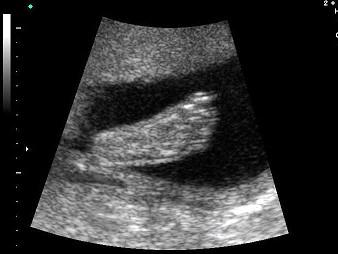

问题 如图,超声显示的是胎儿的哪一部位?(?)

选项 A.手 B.脚 C.腿 D.腹部 E.颈部

答案 B